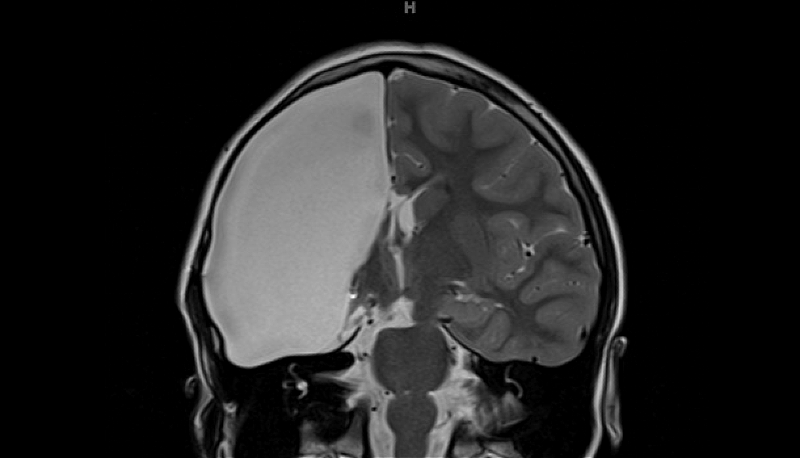

Scientists were baffled because she only had half a brain but had perfect vision

Scientists discovered how a 10-year-old girl born with half a brain is able to see normally through one eye. The youngster, from Germany, has both fields of vision in one eye and is the only known case of its kind in the world. Researchers used an MRI to reveal how the girl’s brain had rewired itself in order to process information from the right and left visual fields in spite of her not having a whole brain. The right hemisphere in the girl’s brain failed to develop in the womb. Normally, the left and right fields of vision are processed and mapped by opposite sides of the brain, but scans showed that retinal nerve fibres that should go to the right hemisphere of the brain diverted to the left. Further, the researchers found that within the visual cortex of the left hemisphere, which creates an internal map of the right field of vision, ‘islands’ had been formed within it to specifically deal with, and map out, the left visual field. (via U of Glasgow)